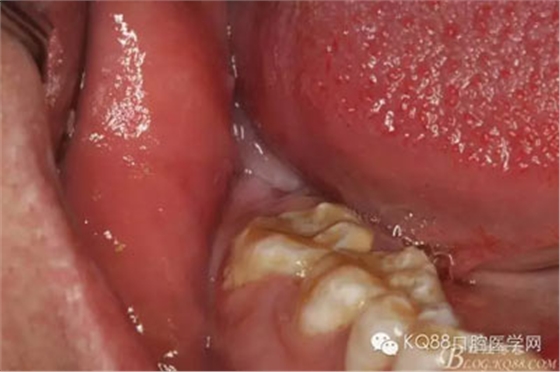

1.術(shù)前的患者口內(nèi)像:48未萌出,無盲袋、頰側(cè)輕度膨隆